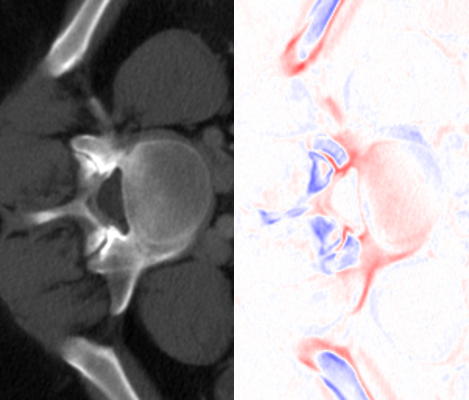

Appendix D Effects of FDM on interpolation results

SAINT generates interpolated slices based on the input of FDM, which is dependent on the voxel spacing of specific slices (as shown in Algorithm 1). We believe that the incorporation of voxel spacing, especially the spacing between slices Rzsubscript𝑅𝑧R_{z}, is important, as it is an indication of how much the details should shift between consecutive slices.

(a) Interpolated Results, Rz=1mmsubscript𝑅𝑧1𝑚𝑚R_{z}=1mm

(b) Interpolated Results, Rz=5mmsubscript𝑅𝑧5𝑚𝑚R_{z}=5mm

Figure 11: Visual comparison of slice interpolation (rz=4subscript𝑟𝑧4r_{z}=4) with different voxel spacing input. Notice how the bone structures change faster for (a) as compared to (b), as the slices are supposed to be further apart according to the respective Rzsubscript𝑅𝑧R_{z}.

To visually understand how changing voxel spacing values impact interpolation results from SAINT, we use AMI to super-resolve the same CT volume with different values of Rzsubscript𝑅𝑧R_{z}, as shown in Fig. 11. We found that through the formulation of FDM, the interpolated slices produce details that change more rapidly if Rzsubscript𝑅𝑧R_{z} is high, and more slowly if Rzsubscript𝑅𝑧R_{z} is low.